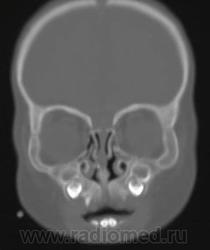

Тричера Коллинза синдром (синдром Томсона, синдром Франческетти; впервые описан в 1846 британским врачом A. Thomson, 1809–1884; в 1900 на офтальмологическом обществе в Лондоне двух пациентов представил британский хирург E. T. Collins, 1862–1932; термин «мандибулофациальный дизостоз» предложен в 1944 швейцарским офтальмологом A. Franceschetti, 1896–1968) – наследственное заболевание, связанное с недоразвитием всей области первой жаберной дуги или первой жаберной борозды. Клинические проявления: наружные углы глаз расположены ниже внутренних; двустороннее недоразвитие скуловых костей и орбит; микрогения; колобомы нижних век; в половине случаев – отсутствие ресниц медиальнее колобомы; микрофтальмия; «птичье лицо»; деформированные ушные раковины; более чем в трети случаев отсутствует наружный слуховой проход; проводящая глухота; преаурикулярные выросты или фистулы; атрезия хоан; увеличение размеров рта; высокое или расщепленное нёбо; врожденные пороки сердца и конечностей; крипторхизм. Тип наследования – аутосомно-доминантный. Выполняют косметические операции по улучшению формы ушных раковин, формированию наружного слухового прохода, возможны слухоулучшающие вмешательства (тимпанотомия с введением слухового аппарата), слухопротезирование.